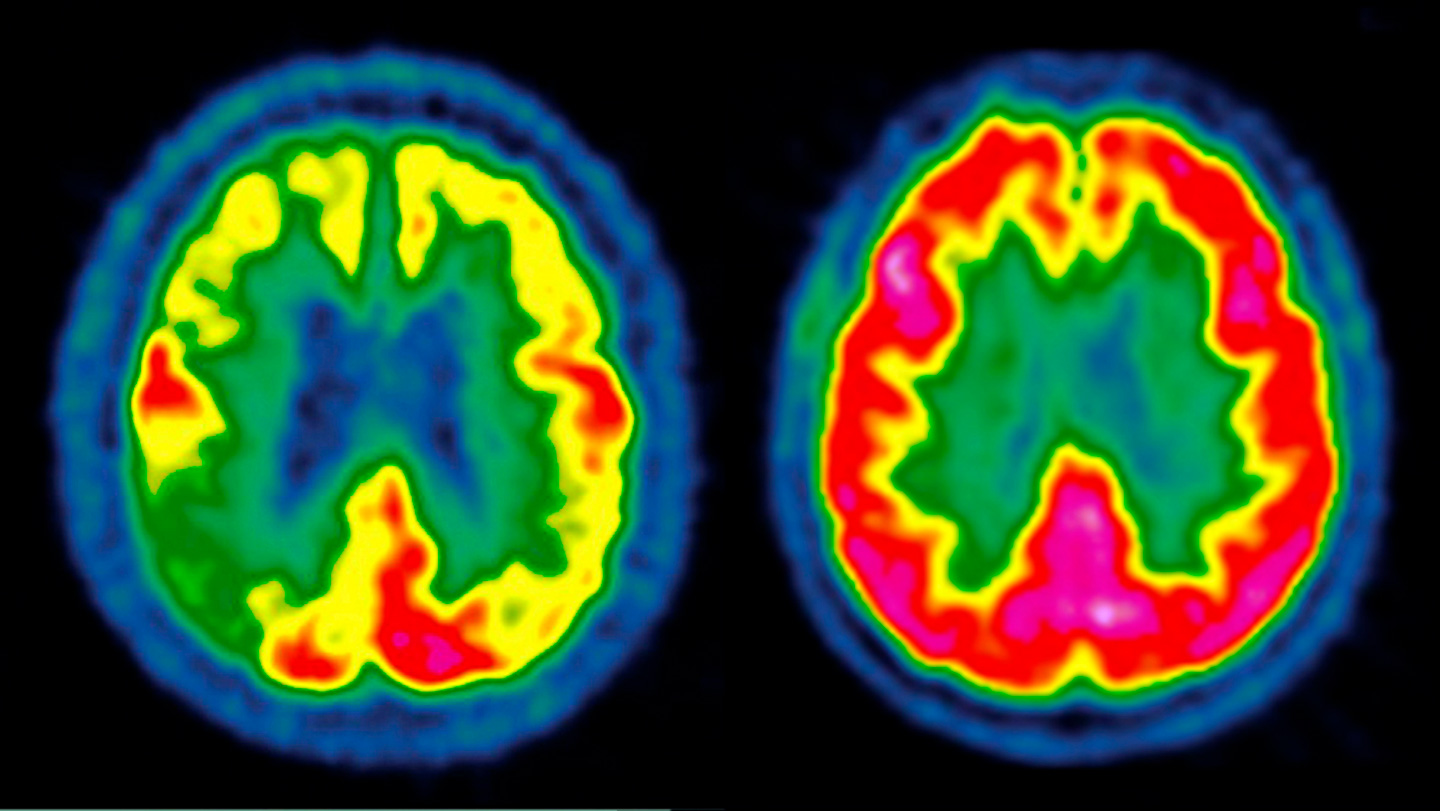

I think this study is demonstrating changes in individuals who already have significant disease.

I think the use of p-Tau 217 / Beta Amyloid 42:40 ratio yields much more as a earlier warning (or if normal reassurance!) in regards to disease, probably 5-10 years or early before MCI occurs. I think that is a valuable piece of data that can be tracked yearly, and will have some individual really pursue everything known to delay disease progression.

Once you have significant disease, which was my take on this EEG study … we don’t have much in the way of action points or levers to pull. I think we do, at the point where a Beta Amyloid 42:40 is abnl, but the p-Tau 217 is still normal … or even if the p-Tau 217 is a little abnormal - this is likely early disease if no MCI … that is a valuable tool letting individuals know they must get very serious about everything.